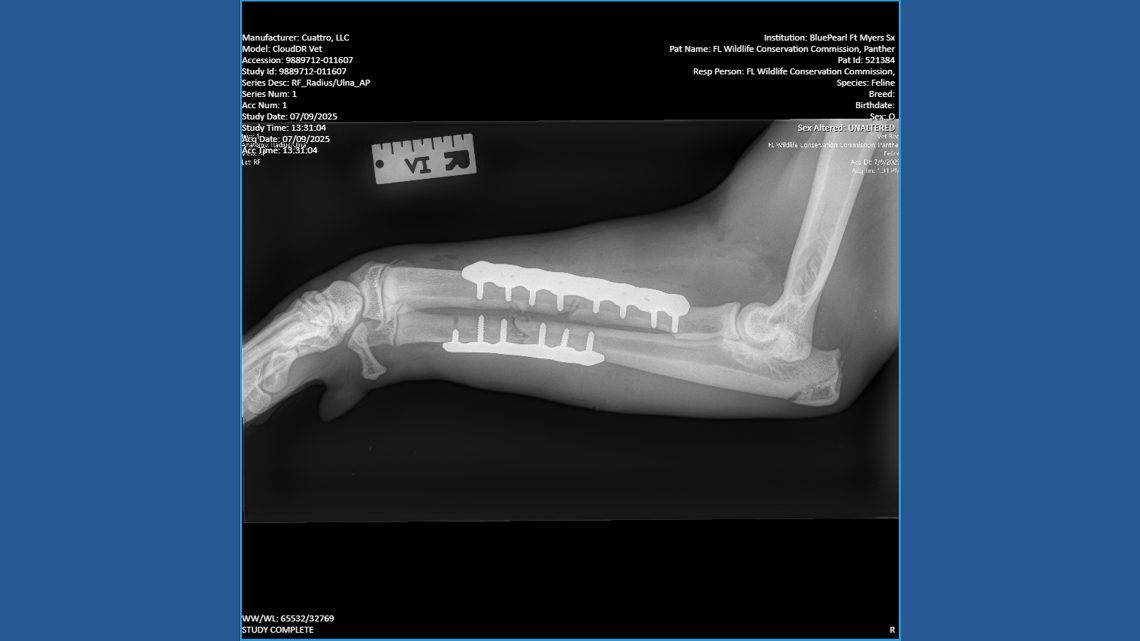

The Florida Fish and Wildlife Conservation Commission coordinated an emergency response, which led to the big cat having surgery at BluePearl Specialty and Emergency Pet Hospital in Fort Myers. There, veterinarians treated fractures, according to staff in the zoo.

“Following initial assessment and stabilization, the panther was found to have sustained a right radius and ulna fracture as well as some minor lacerations. We were able to stabilize both bones with plates and screws to repair the injuries,” Dr. Oscar Carballo, at BluePearl in Fort Myers, said. “We were delighted the panther was transferred to ZooTampa for recovery.”